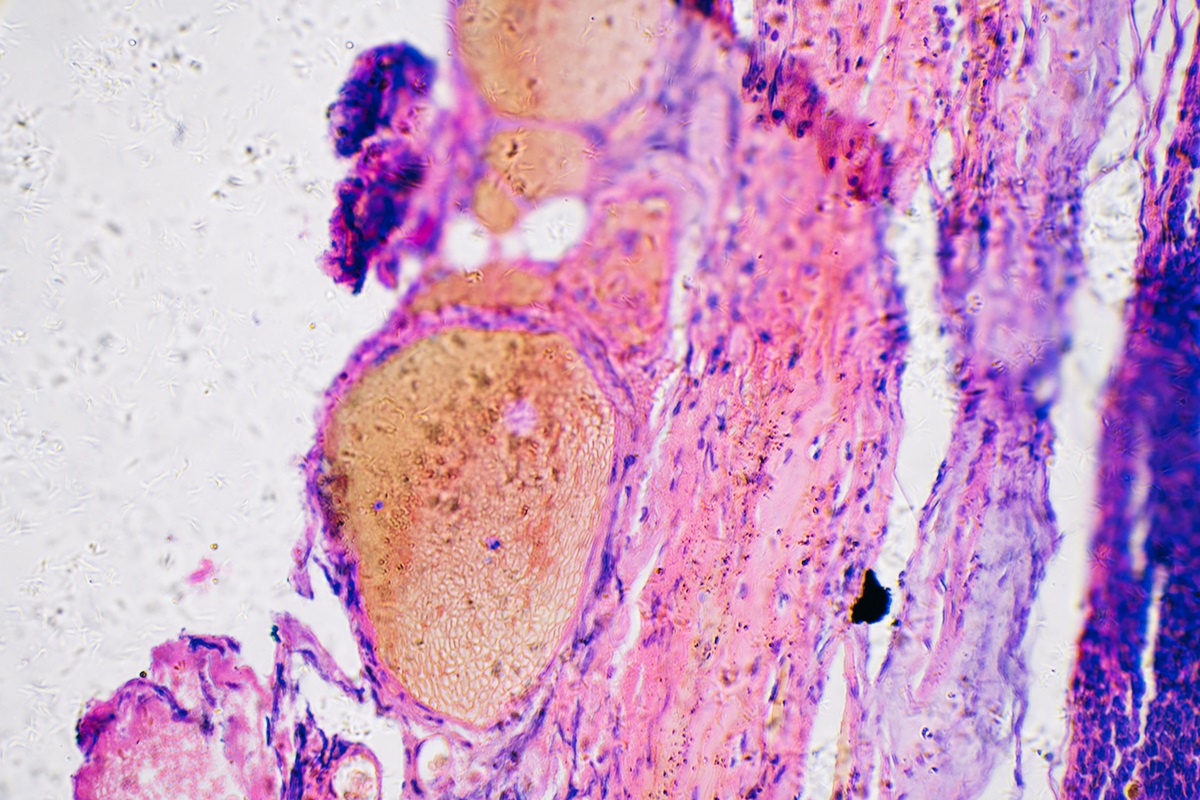

O câncer de pele é dividido em dois grupos principais: melanoma e não melanoma.

O tipo não melanoma, que inclui os carcinomas basocelular e espinocelular, é o mais comum e geralmente está relacionado à exposição solar acumulada ao longo da vida. Quando identificado precocemente, as chances de cura ultrapassam 90%.

Já o melanoma é menos frequente, porém mais agressivo, com maior risco de metástases. Por isso, qualquer lesão nova ou mudança em manchas já existentes deve ser investigada por um dermatologista, com confirmação diagnóstica feita por biópsia.